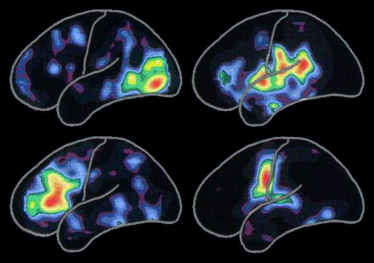

左の陽電子断層撮影法(PET)スキャンは、以下に関連する脳の活動の標準的なパターンを示します。

活動は、赤の領域で最高潮に達し、黄色から青紫の他の虹色に変化するにつれて、減少します。

特定の活動パターンは、新しく人と知り合ったり、新たな経験をしたり、新しいスキルを獲得したりしながら、生涯にわたって変化します。また、このパターンは、アルツハイマー病または関連疾患が神経細胞や結合を次々に破壊するときも変化します。